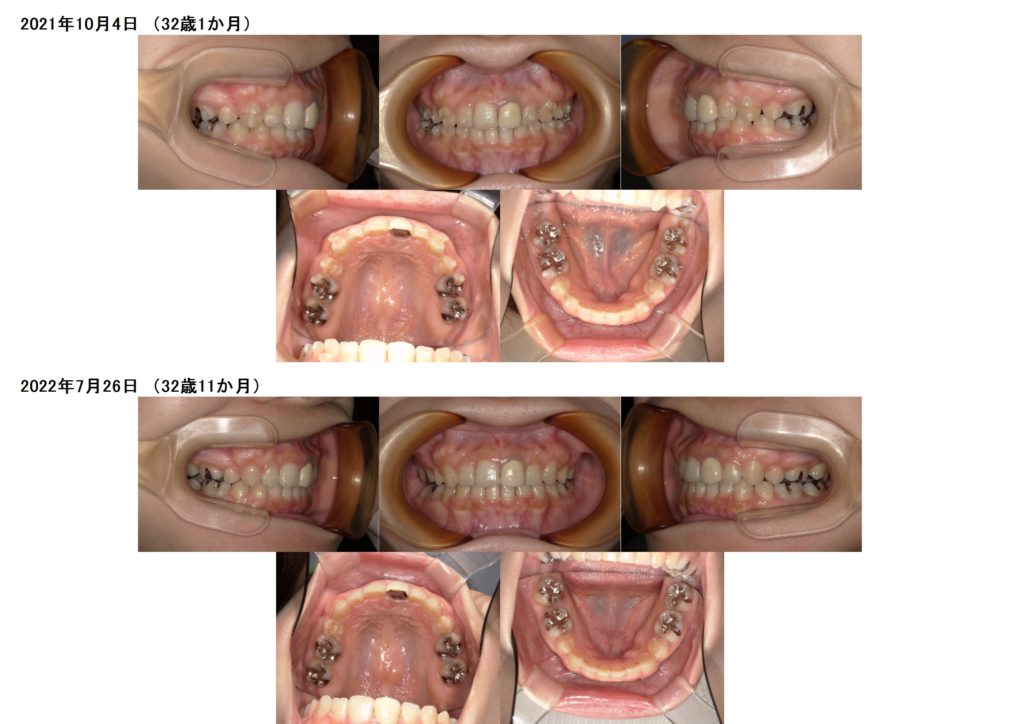

微調整に入ると、少しずつの変化になりますが、見比べてみると全く違いますよね。

患者様にはとっても長く感じる期間かと思いますが、重要な期間でもあるのでしっかりと使用時間を守って

マウスピースを使っていただきたいです!!